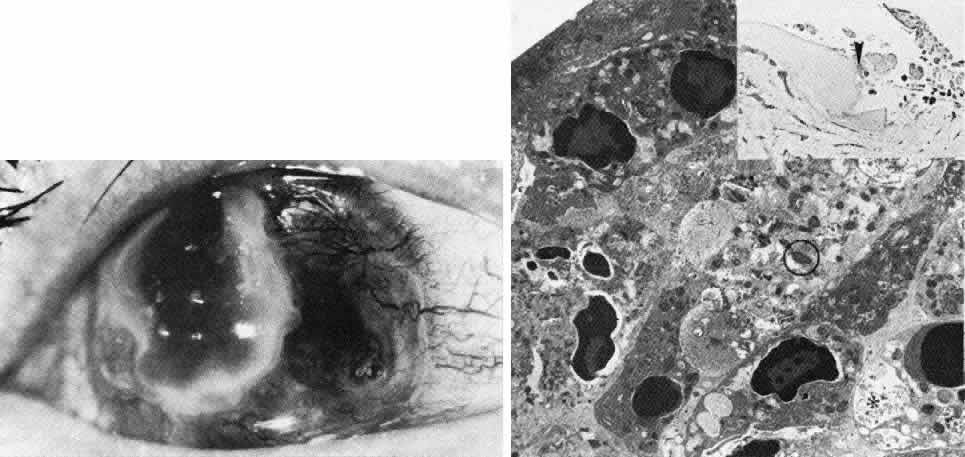

Color Plate 1 A. Rieger's anomaly. The central cornea is unaffected and visual acuity remains normal. However, there is anterior displacement of Schwalbe's line and broad iridocorneal synechiae with distortion and displacement of the pupil. B. Peters' anomaly. The corneal leukoma is central, corresponding to the defect in Descemet's membrane and endothelium with overlying stromal disorganization. The peripheral cornea remains clear. Not evident are characteristic adhesions between the iris margin and the periphery of the stromal opacity. C. Congenital anterior staphyloma. Extreme stromal ectasia, scarring, and disorganization plus neovascularization are accompanied by congenital glaucoma with anterior buphthalmos. The posterior segment remains relatively unaffected. D. Epithelial basement membrane dystrophy, This variant of map-dot-fingerprint dystrophy displays predominantly small, opaque debris-filled intraepithelial pseudo-cysts, with predisposition to recurrent erosive symptoms. E. Band keratopathy. In this patient with long-standing chronic inflammation subsequent to multiple surgical procedures, extensive calcific deposition at the level of Bowman's layer results in epithelial distortion and erosion. F. Granular corneal dystrophy. This autosomal dominant dystrophy displays discrete stromal opacities with the appearance of snow-flakes or bread crumbs, and since the intervening stroma is clear, visual acuity is maintained. G. Lattice corneal dystrophy. This autosomal dominantly inherited disorder of amyloid metabolism is evident as pathognomonic branching opacities within the corneal stroma, as well as more diffuse subepithelial deposits, best appreciated by retroillumination. H. Macular corneal dystrophy. This autosomal recessive dystrophy displays diffuse full-thickness stromal haze with superimposed focal stromal opacities, affecting both stroma and Descemet's membrane. Since vision is compromised, penetrating keratoplasty is required. I. Central crystalline dystrophy (Schnyder). Fine, needlelike intrastromal crystals, predominantly of cholesterol, are slowly progressive and may be accompanied by arcus. The dystrophy is dominantly inherited and may have concomitant systemic abnormalities of lipid metabolism. J. Congenital hereditary endothelial dystrophy. Diffuse edema of the corneal stroma is accompanied by relatively limited and usually nonprogressive epithelial edema. Thus, visual acuity may be relatively well preserved. K. Fuchs' endothelial dystrophy. The earliest manifestations are evident as myriad focal guttate excrescences of Descemet's membrane in the absence of epithelial or stromal edema. These are best appreciated by retroillumination, and specular microscopy is confirmatory (see also Fig. 17). L. Fuchs' endothelial dystrophy. With a more advanced stage of corneal endothelial dysfunction, stromal and epithelial edema progress with loss of vision and possibly painful bullous epithelial erosion. M. Posterior polymorphous dystrophy. In this moderately advanced case, grouped vesicular opacities at the level of Descemet's membrane probably correspond to fibrous proliferations in the geographic areas of endotheliallike transformation. There is some extent of stromal edema, but visual acuity is usually preserved. N. Keratoconus. The corneal thinning and ectasia result in extensive visual distortion due to irregular astigmatism. O. Terrien's marginal degeneration. In this young man with progressive myopic astigmatism, noninflammatory corneal thinning is evident in the superior periphery. Noteworthy slit lamp findings include neovascularization of the thinned stroma with lipid extravasation at the leading edge without epithelial defect. P. Mooren's ulcer. This inflammatory condition of peripheral ulcerative keratitis is hall-marked by pain in the setting of intense conjunctival inflammation. The overlying peripheral corneal epithelium is ulcerated, as is the corresponding stroma. A dense infiltrate of acute inflammatory cells precedes the active front of progressive ulceration. This case was remarkably improved by simple resection of the adjacent peripheral limbal conjunctiva.